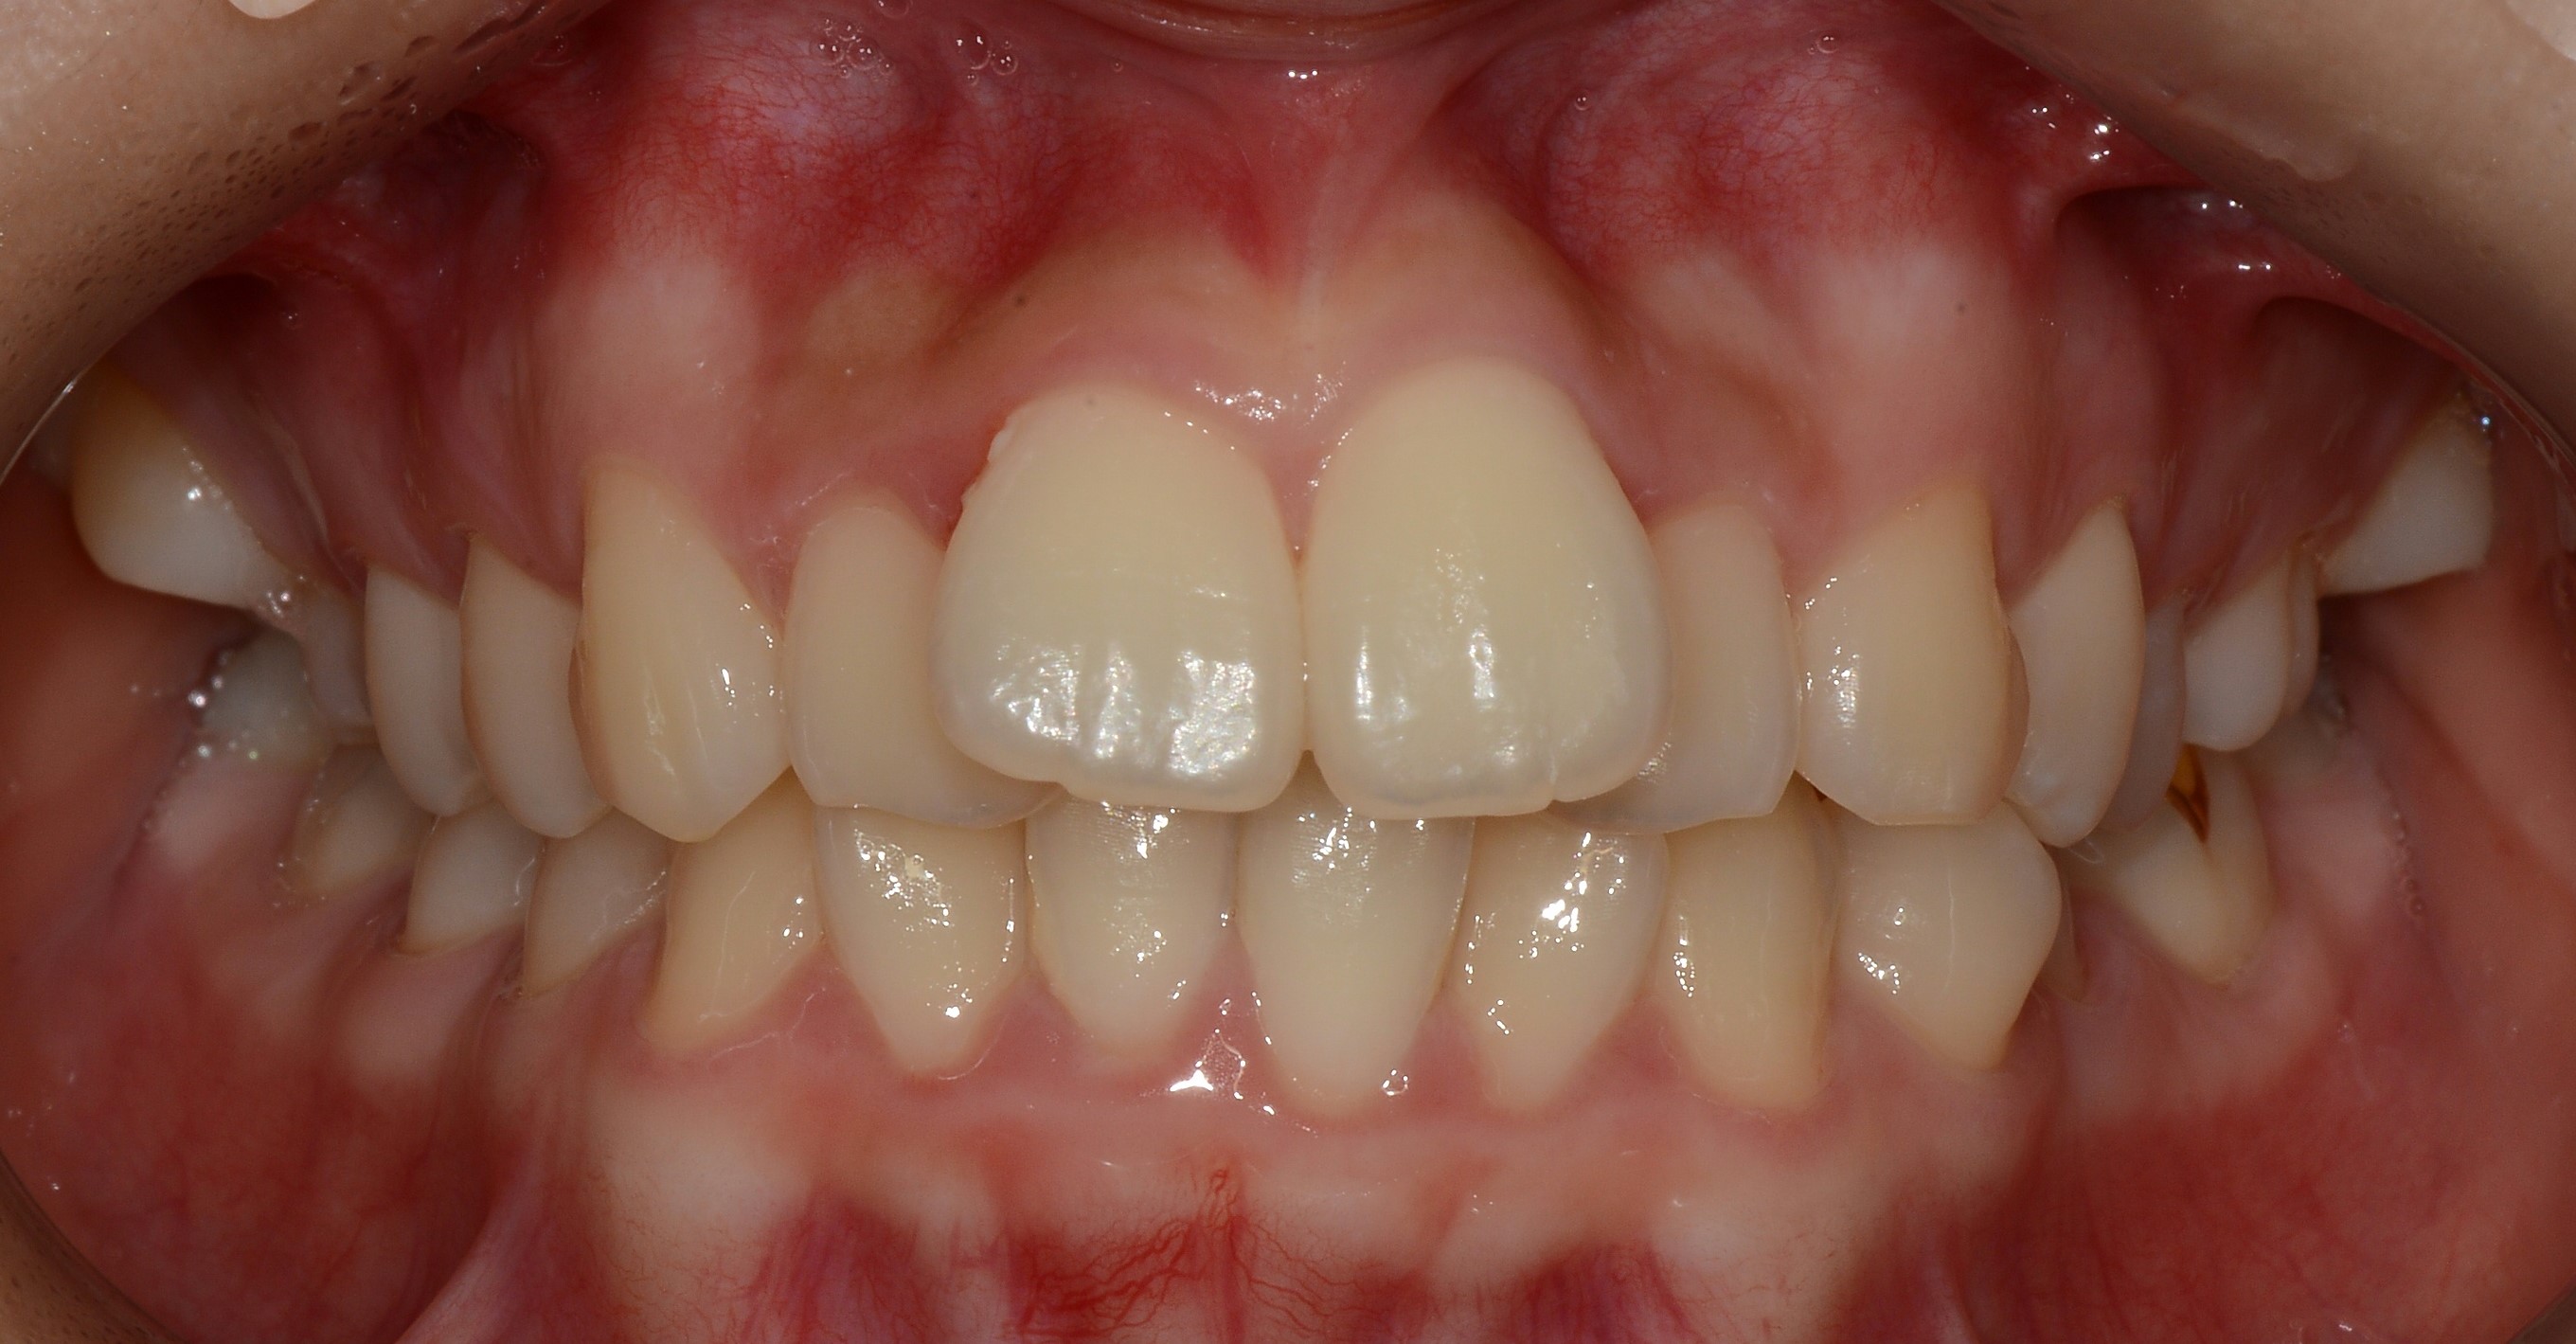

치료 전 사진입니다.